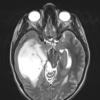

NEOPLASMS (GLIAL)

Astrocytoma, IDH-mutant, WHO Grade 2